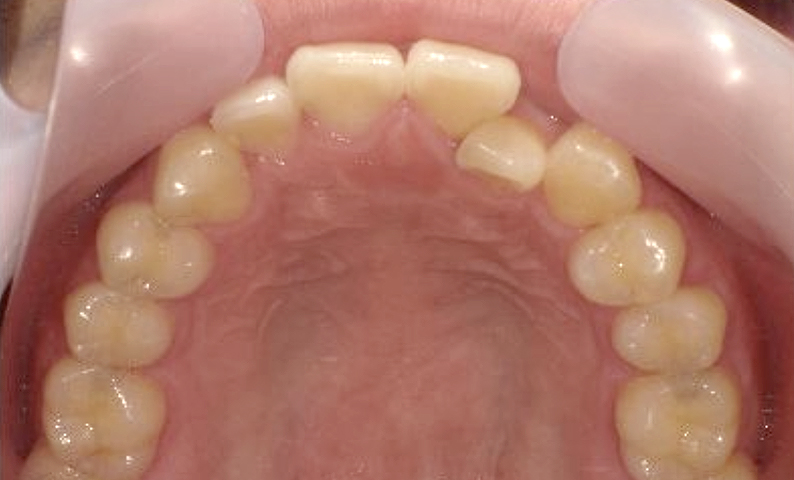

症例_018 上顎だけの部分矯正

治療期間:7ヶ月金額:30万円+税女性前歯のガタガタ上の前歯だけ

| Before | After |

|---|---|

|